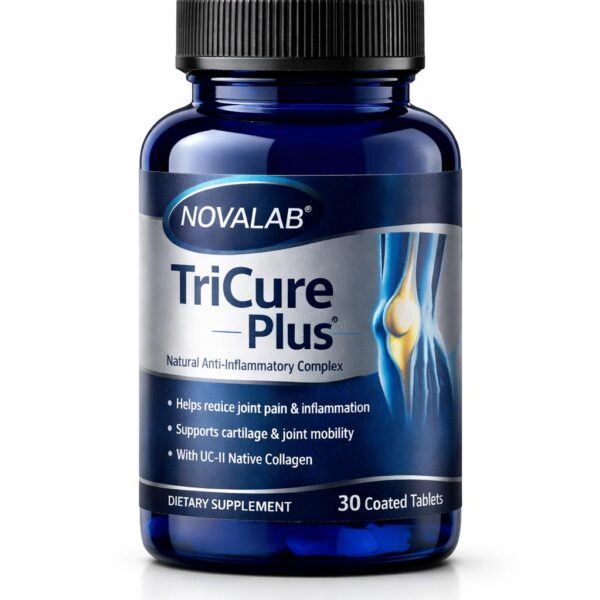

Featured Products

Select options This product has multiple variants. The options may be chosen on the product page